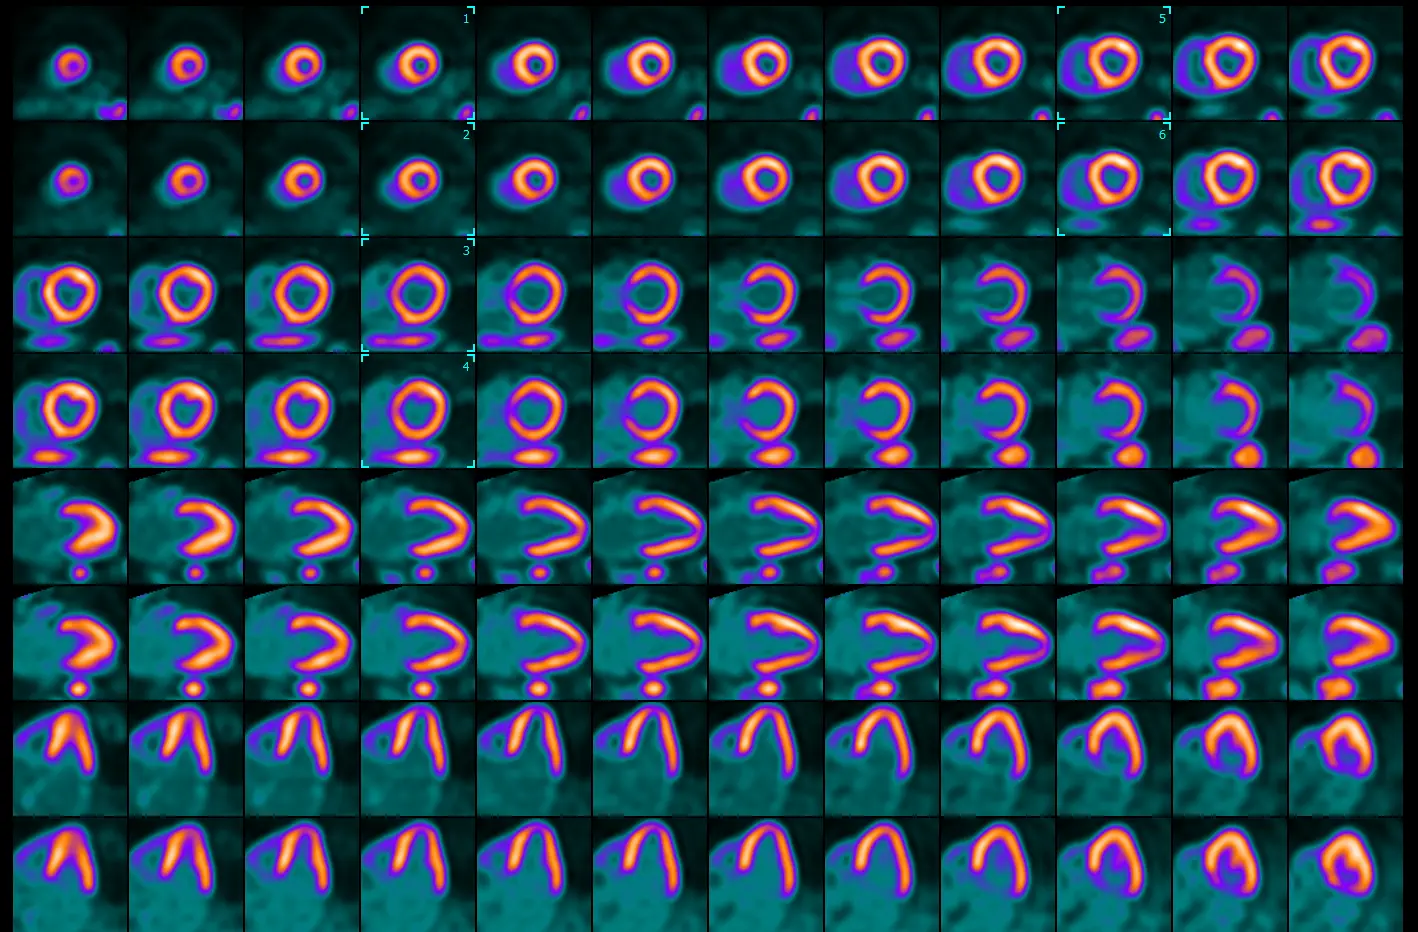

Identifying the level - apex, mid, base

- Select the apex: Sperry identifies will scroll to identify the bottom at the apex is lined up in both the stress and rest images. He then places the box (🔲) two slices above this by clicking

Ctrland selecting these frames. - Select the base: identify the frame where you first lose the septal wall → shift a couple frames apically and place the box (🔲) over these frames

- ⚠️ important to recognize that the way we orient the heart in these images that top of the basal portion of the septal wall doesn’t exactly line up with that of the lateral wall. Don’t neglect perfusion defects in the basal lateral walls!

- Select the mid: find the frame in between your apical and base boxes (🔲) → place the box (🔲) over these frames